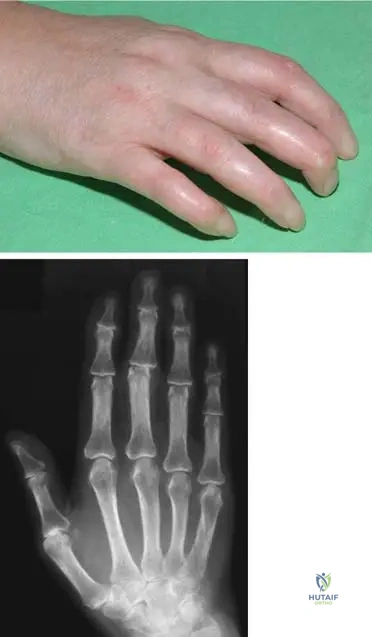

A 42-year-old female presents with a 3-month history of bilateral hand and foot pain, swelling, and morning stiffness lasting approximately 2 hours. Physical examination reveals symmetrical swelling and tenderness in the metacarpophalangeal (MCP) and proximal interphalangeal (PIP) joints of both hands, as well as mild swelling in both knees. Serum rheumatoid factor is elevated.

View Answer & Explanation

Correct Answer: D

Rationale: The vignette describes several criteria for rheumatoid arthritis (RA) diagnosis according to the American Rheuma Association (ARA) simplified criteria: morning stiffness (minimally 1 hour, lasting for more than 6 weeks), arthritis of hand joints (lasting for more than 6 weeks), and symmetrical arthritis (lasting for more than 6 weeks). While rheumatoid nodules are a criterion for RA, their presence is not required for diagnosis, and the patient's current presentation does not include them. The other options (A, B, C, E) describe conditions that would argue against a diagnosis of confirmed RA based on the ARA criteria (e.g., morning stiffness <1h, <3 joint areas, asymmetrical, <6 weeks duration). The main distractor, A, is incorrect because morning stiffness must be at least 1 hour for RA diagnosis.

Question 74

A 38-year-old female presents with early symptoms of rheumatoid arthritis. Radiographs of her hands are obtained to assess for initial changes. What is a typical early radiographic finding in rheumatoid arthritis?

Correct Answer: C

Rationale: Early radiographic changes in rheumatoid arthritis typically include soft tissue swelling, juxta-articular osteopenia (often described as striped periarticular atrophy or osteoporosis), and marginal erosions. Diffuse osteosclerosis, joint space widening, large subchondral cysts, and carpal ankylosis are not characteristic early findings; ankylosis is a late-stage change. The main distractor, A, is incorrect as osteosclerosis is not an early feature of RA; rather, osteopenia is seen.